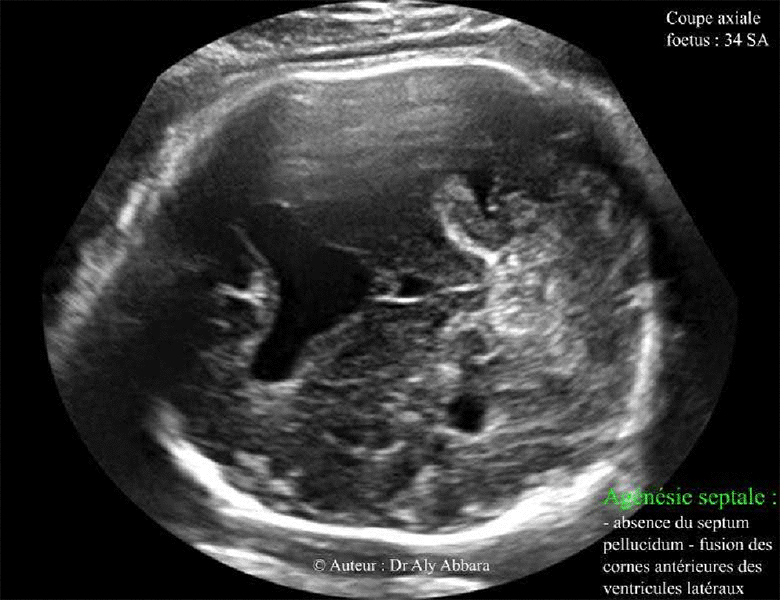

Agénésie septale totale - Foetus de 34 SA

Agénésie septale caractérisée par l'absence du septum pellucidum et la fusion des

cornes antérieures des ventricules latéraux

Images échographiques : coupe axiale